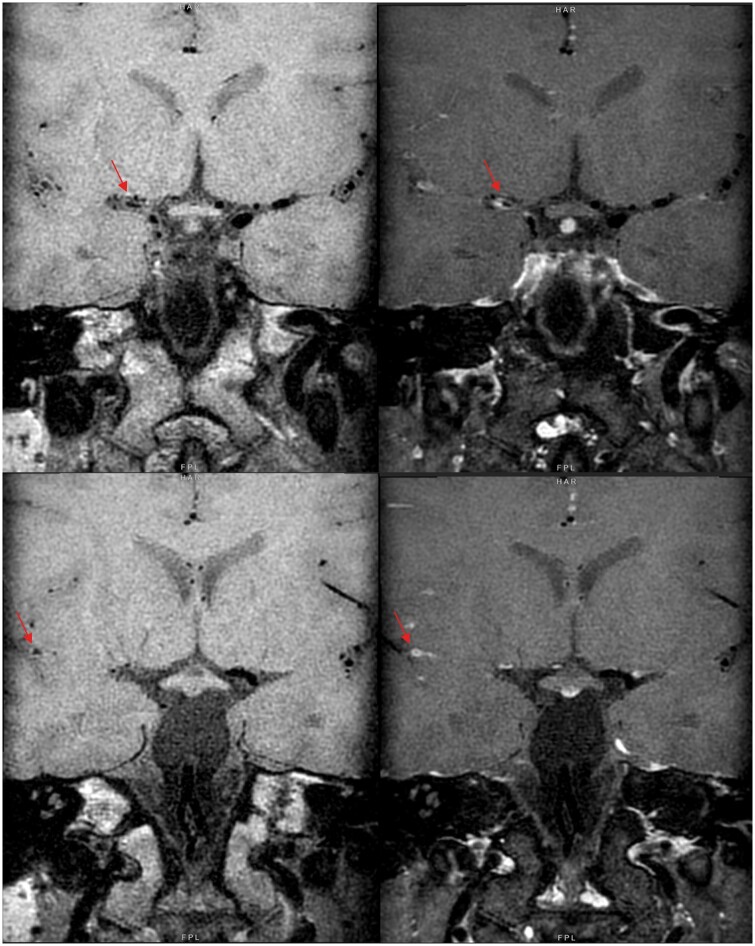

Abstract Image